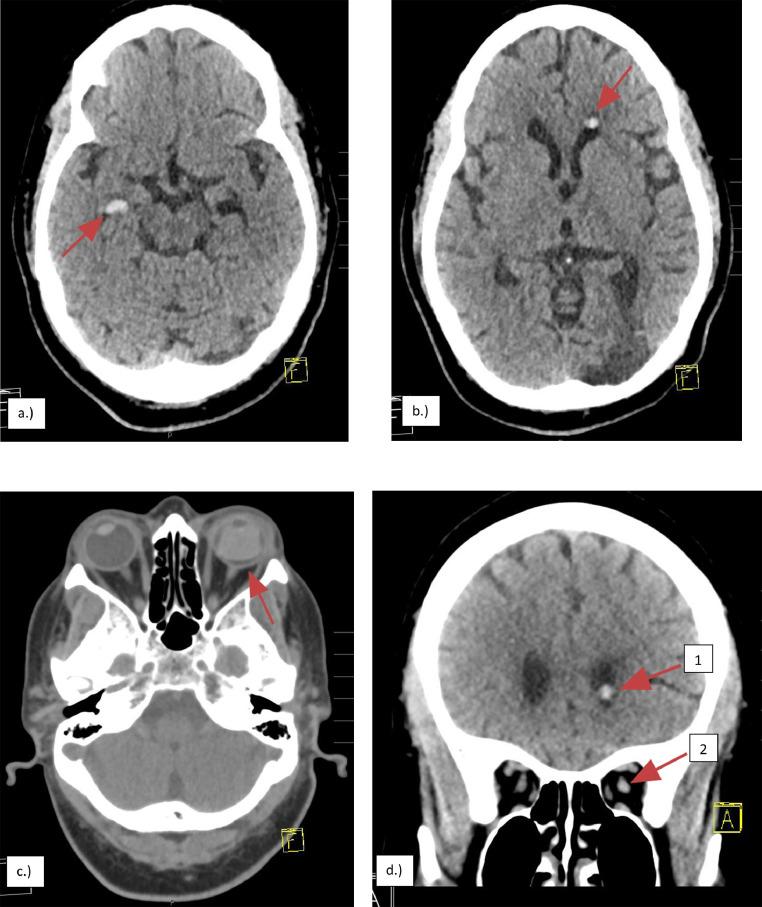

Here we describe two, separate, and unique radiological findings in two distinct patients, sequelae from prior silicone oil injection for management of retinal detachment. In both cases we present bilateral, frontal horn hyperdense "masses" without appreciable enhancement or surrounding vasogenic edema. Both cases serve as important reminders of the potential for silicone oil migration and its unique radiological presentation, which has the potential to be a radiologic mimic of intracerebral hemorrhage and significantly change medical management of individuals presenting with transient ischemic attack or cerebrovascular accident.

在此,我们描述了两名不同患者身上出现的两种独立且独特的放射学表现,这是先前为治疗视网膜脱离而注射硅油的后遗症。在这两个病例中,我们均发现双侧额叶角有高密度“肿块”,无明显强化或周围血管源性水肿。这两个病例都有力地提醒我们,硅油有迁移的可能性及其独特的放射学表现,这有可能在放射学上被误诊为脑出血,并显著改变患有短暂性脑缺血发作或脑血管意外患者的医疗管理。